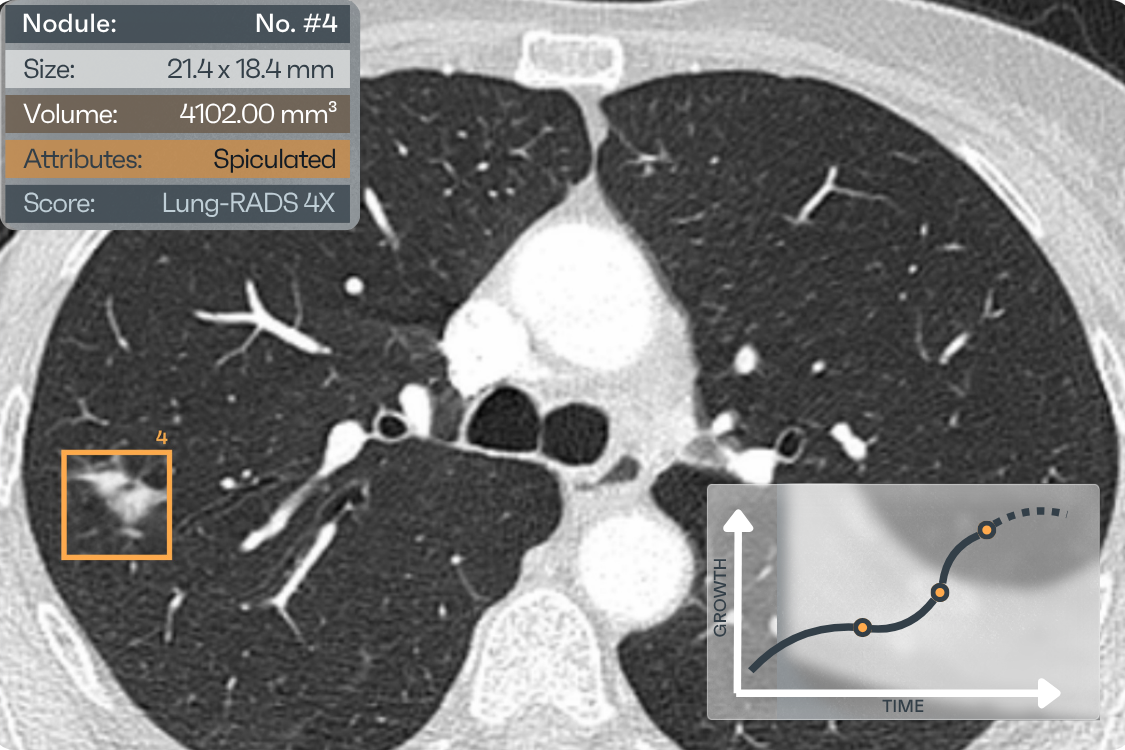

NODULE INFORMATION